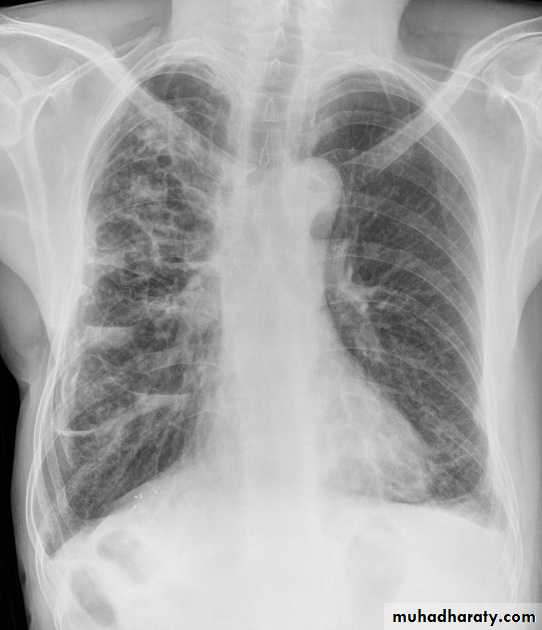

Interstitial pulmonary edema

Pulmonary edema ( alveolar pulmonary edema)

Bat wing sign ( alveolar pulmonary edema)

38.interstial pulmonary edema

39.pulmonary edema ( alveolar pulmonary edema )

40.batwing sign ( alveolar pulmonary edema )